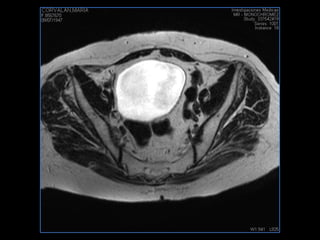

PROTOCOLO pelvis SAG T2, Y FAT SAT (FINOS) AXIAL T1  AX FAT SAT CON   GADOLINIO :  AX T1 Y COR T1 SAT: NO  FASE: RL THK: 3MM  COIL:  GAP: (FACTOR 1.4) 1MM FOV: 40 CM NEX:2 SINCRONIZACION RESPIRATORIA EN 3 O 4 CICLOS ALE

resonancia de abdomen